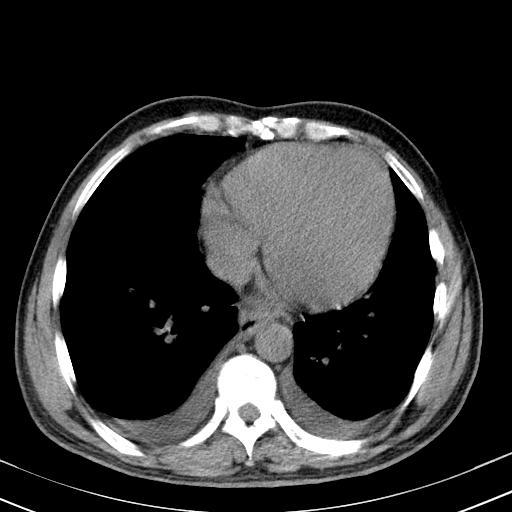

以下是引用zxl51642在2010-3-21 17:06:00的发言:[br]右下中心型肺癌并阻塞性肺炎/不张,纵膈淋巴结肿大,右侧大量胸腔积液,左侧少量胸腔积液,少量腹水。建议纤维支气管镜进一步检查。